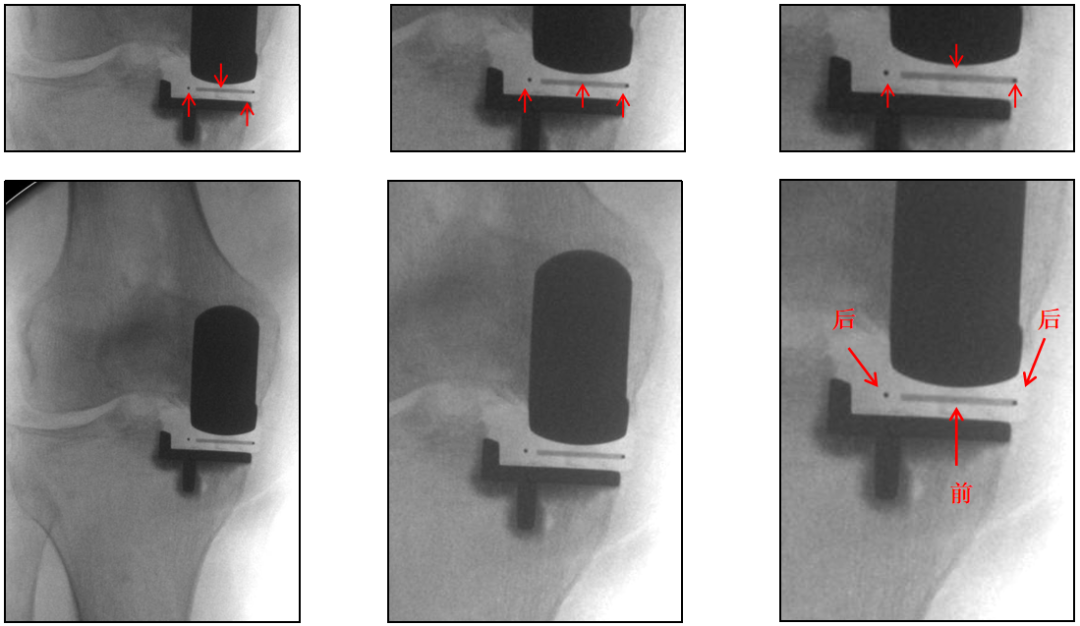

辨认bearing内的标识(透视片侧位)

bearing 内的标识:点和线段“ .—. ” 线段显示为“—”在前;点显示为“.”在后

辨认bearing内的标识( X-ray正位)

bearing 内的标识:点和线段 “ .—. ” 线段显示为“—”在前;点显示为“.”在后

辨认bearing内的标识(X-ray侧位)

bearing 内的标识:点和线段“ .—. ”线段显示为“—”在前,点显示为“.”在后